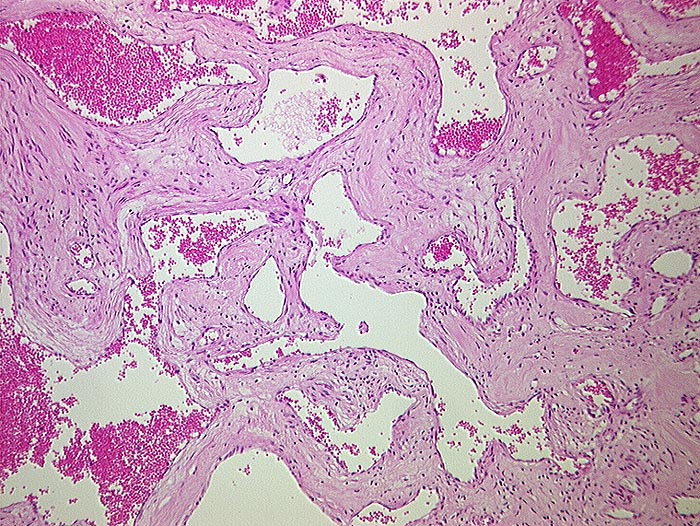

PathoPic ID 898 - Kavernöses Hämangiom

Kavernöses Hämangiom

benigner Tumor

Leber

Leber, Gallenwege, Pankreas

Tumor aufgebaut aus ektatischen Gefässen.

Tumordurchmesser 10cm.

Histologie